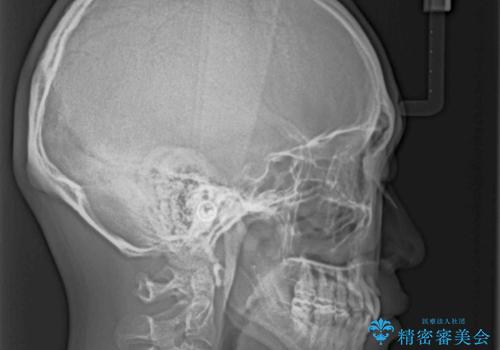

下顎骨が左側に大きく変位しているため、上下の正中位置は極力一致するところをゴールとしました。

上下顎で左右差の大きい抜歯矯正を裏側装置で行ったため、非常に時間がかかりましたが、正中位置も良い位置に改善され、気になっていた突出感も解消されました。